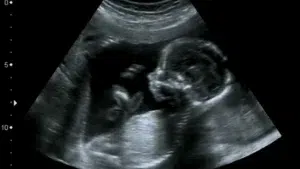

La muerte fetal intrauterina, también llamada óbito fetal, es la muerte del feto antes de su expulsión o extracción en el nacimiento y, según la Organización Mundial de la Salud (OMS), es independiente de la duración del embarazo.

Sebastiana Marcelino aseguró que cuando su nuera llegó al hospital la bebé aún se movía; minutos después, personal de ese nosocomio le informó que la neonata había fallecido.